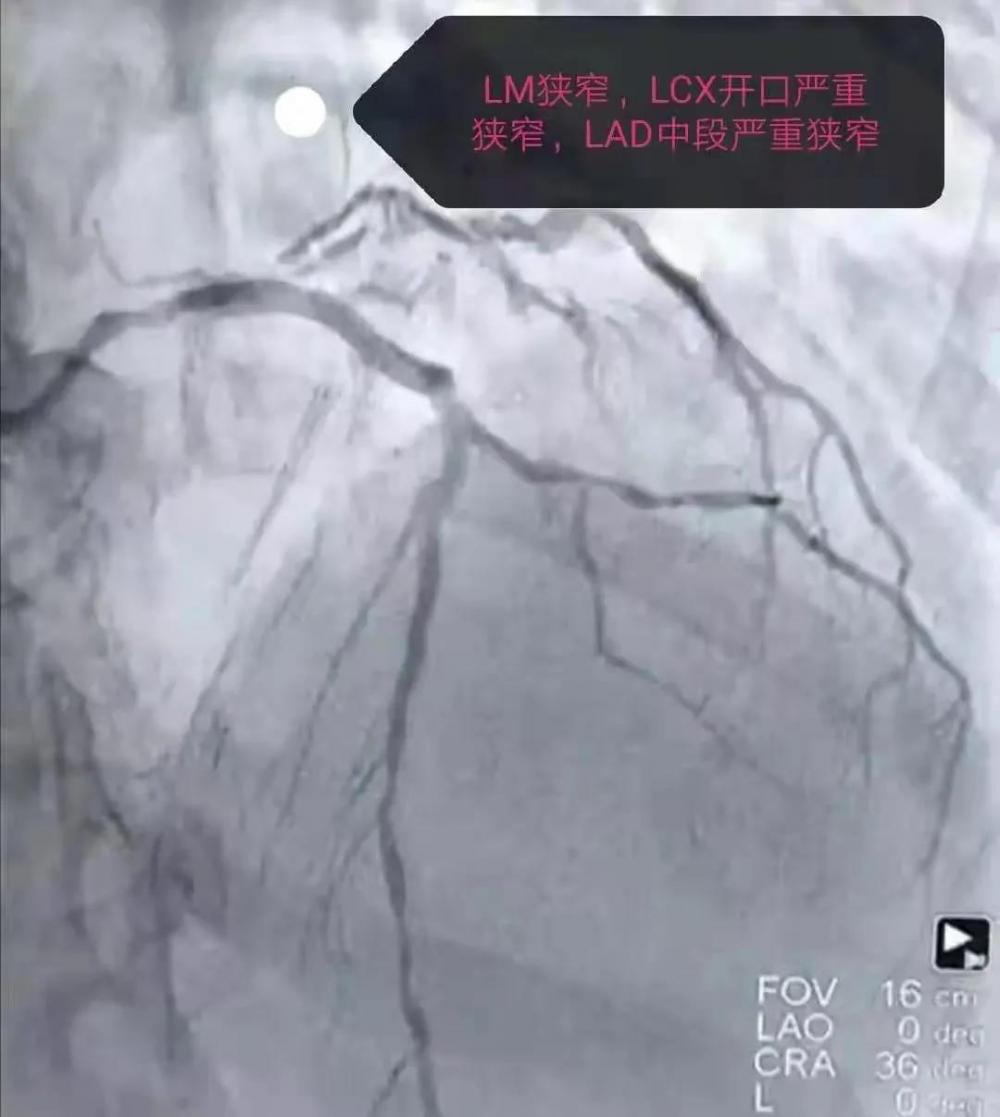

大约30分钟冠脉造影检查出来了。

术前

结合心电图、患者病史及冠脉造影可以明确患者既往有前壁心肌梗死,并且已经行介入支架治疗(支架通畅),此次为急性下壁心肌梗死,三支冠状动脉血管均有病变,RCA完全闭塞,再次取得病人及家属的同意后,急诊快速开通血管。